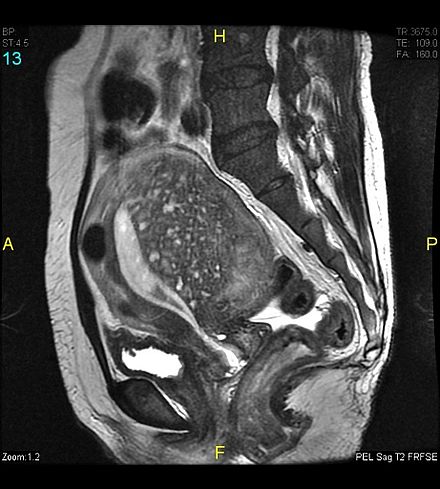

Các dấu hiệu chẩn đoán adenomyosis trên MRI bao gồm:

- Tử cung dạng hình cầu, bờ đều

- Thành tử cung dày không đồng đều (thành trước thường dày hơn thành sau)

- Vùng nối (junctional zone – JZ) dày >= 12 mm

- Tỷ số giữa toàn bộ cơ tử cung và vùng chuyển tiếp lớn nhất > 40-50% (liên quan đến tăng sinh tuyến lớp cơ tử cung)

- Vùng tăng tín hiệu tập trung dọc theo nội mạc tử cung trên T2 và đôi khi thấy trên T1 xóa mỡ - là hình ảnh của tuyến chứa dịch hoặc có thể có xuất huyết.